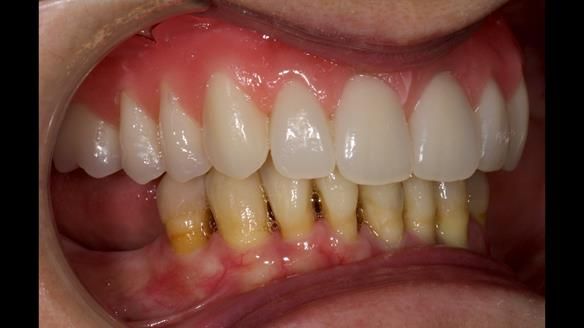

She had previously suffered from generalised periodontitis – stage IV, grade C, currently stable, with reduced attachment across the upper arch.

By the time she came to me, her periodontal condition was stable — but the aesthetics in the upper jaw were very poor.

Dr Syed Abad — my colleague and a Specialist in Periodontics — had successfully stabilised her gum health.

We provided her with an immediate upper denture (Mk 1), followed by a definitive metal-based upper denture (Mk 2). A lower removable partial denture was discussed, to be made only if needed once the upper treatment was complete. However, at review, this wasn’t necessary — Adnana had excellent neuromuscular control and function, even with a shortened dental arch (SDA).